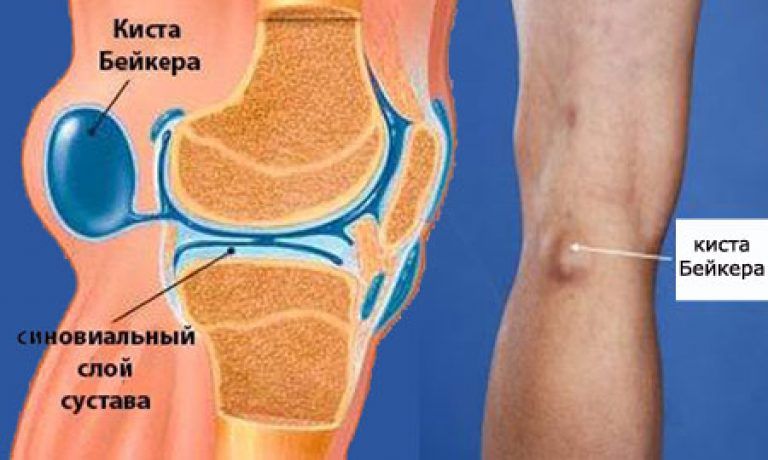

Анатомия коленного сустава: изучение анзерита и его влияния